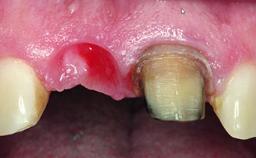

A healthy 28-year-old female patient presented for a consultation on treatment options to restore her upper right central incisor. At the clinical examination, the tooth responded to percussion and palpation. The gingiva was red and slightly swollen, with a mid-facial probing depth of 10 mm. The upper right lateral incisor showed no signs or symptoms, did not respond to exploration and percussion, and the vitality test was positive. The periapical radiograph revealed that tooth 11 had been endodontically treated, with no lesion evident at the apex. A small radiopaque calcified structure surrounded by a narrow radiolucent zone (3 × 3 mm) was present at the apex of tooth 12.

Soft Tissue Anatomy Intact Defective

Soft Tissue Contour and Volume Slightly compromised